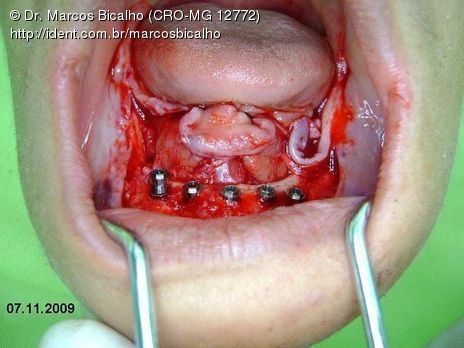

Protocolo Inferior com 5 Implantes - Parte I - Planejamento + Cirurgia

Apesar da boa adaptação e estética satisfatória, a principal queixa da paciente era a instabilidade da prótese inferior, como sempre ocorre nestes casos...atrofia do rebordo alveolar e perda da função mastigatória.